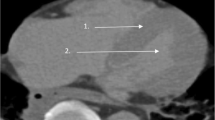

Post-mortem computed tomography

Each post-mortem case underwent a non-contrast CT scan (Siemens SOMATOM Scope, Healthineers AG, Germany) of the head and torso prior to examination. Heart volume was determined by manual tracing of the pericardial sac in several axial slices (3 mm) between the first piece of the superior tip of the right atrial appendage (upper bound) and the visualization of the right coronary artery inferior to the right atrium (lower bound). If the right coronary artery was not visible inferiorly, the inferior atrioventricular groove was used as the lower bound. Measurements were made using 3D Slicer software [10], which interpolated between traced segments. This software is open access and does not require specialized equipment (https://www.slicer.org/).